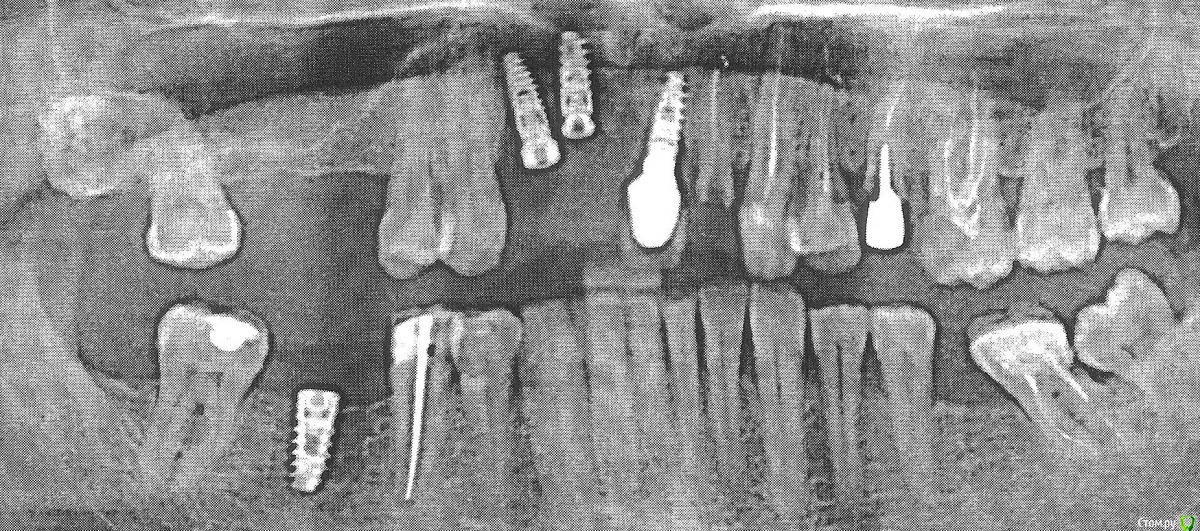

ablom Опубликовано 10 декабря, 2019 Поделиться Опубликовано 10 декабря, 2019 Здравствуйте и большое спасибо врачам, помогающим форумчанам.На взгляд пациента-дилетанта, читавшего форум, в моем случае весь набор - не хватает кости, имплантаты плохо позиционированы и стоят близко. Мне 55 лет, здоровья и денег на нормальное протезирование нет, единственная реальная возможность для меня заработать их - публичные выступления, где надо много рассказывать. Но без передних зубов и сам я смущаюсь, и слушатели будут смеяться. Помогите по снимку оценить шансы возможным коронкам удержаться хотя бы год. Может быть, хоть пласмассовые можно? Ссылка на комментарий

Bier Опубликовано 10 декабря, 2019 Поделиться Опубликовано 10 декабря, 2019 ситуация решаемая, нужно убрать средний имплантат и сделать мост на 2х имплантатах, либо на 1м имплантате 2 коронки. Так можно. 2 Ссылка на комментарий